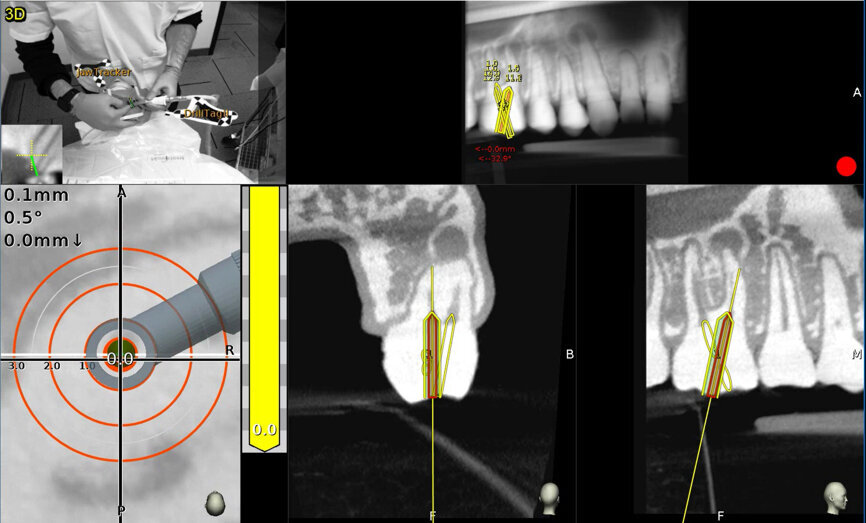

Fig. 3: The screen is divided into (1) panoramic view, (2) 3D reconstruction, (3) axial view, and (4) buccolingual and (5) mesiodistal section views.

Fig. 9a: Calcified central incisor: (1) the drill is green; (2) the central axis of the glide path or osteotomy; (3) the depth indicator; (4) the angle between the drill and central axis of the planned osteotomy. When the drill and the central axis overlap, the depth indicator turns yellow. (Courtesy of Dr Bobby Nadeau)

Fig. 9b: Maxillary molar: the planned canal location is on target (yellow: 0 mm). (Courtesy of Dr Bobby Nadeau)

Dentoosseous real-time navigation

The navigation screen is active when the system identifies the calibrated instrument as it approaches the patient’s jaw. The target view measures the distance between the instrument’s tip and central axis of the designated access penetration point, the glide path or the osteotomy. The central axis length of the planned procedure is represented by the centre of the static white target, and the tip of the drill is in dicated by the moving black cross following the drill tip movement. The real-time direction of the drill is represented as a cone in the head of the handpiece (Figs. 9a & b).

During the drilling, the moving cross and cone are tracked. The cone will turn green when the instrument tip is within 0.5 mm and has an angulation of less than 3° to the planned glide path or osteotomy. When the drill tip reaches a distance of 1 mm from the apical or horizontal extent of the planned depth landmark, the depth indicator turns yellow.